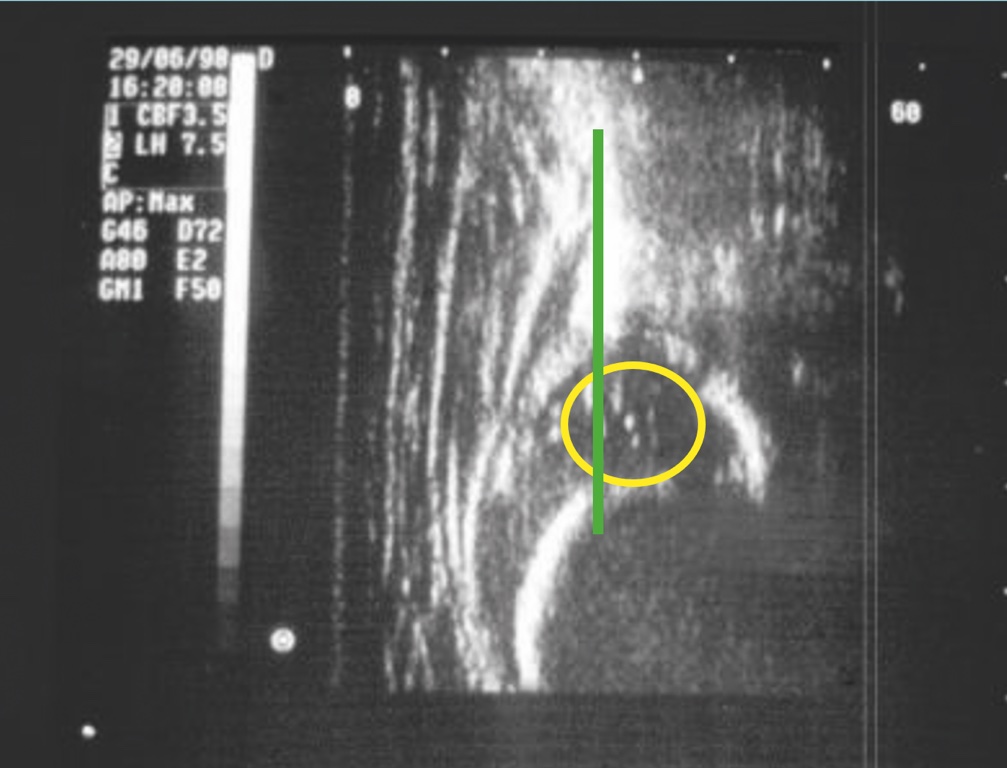

Oltre ai test clinici descritti che permettono un precoce sospetto diagnostico della displasia, viene comunemente utilizzato l’esame ecografico che ormai rappresenta un test estremamente affidabile; tale test, sebbene non ancora obbligatorio, viene praticato come screening diagnostico dalla quasi totalità dei neonati intorno alla ottava settimana di vita. Lo screening ha lo scopo di evidenziare casi di displasia non sospettati con l’esame clinico alla nascita che può risultare negativo anche se correttamente praticato. Nei casi in cui è presente una familiarità della patologia o i test di Ortolani/Barlow risultino positivi alla nascita, l’esame ecografico deve essere praticato per confermare il sospetto diagnostico nei primi giorni di vita. La diagnostica precoce della displasia evolutiva dell’anca permette di trattare conservativamente la patologia nel corso dei primi mesi di vita o comunque prima dell’inizio della deambulazione scongiurando l’evoluzione della patologia (Figg. 2-4).

L’esame ecografico è stato introdotto negli anni 80 da Graf che ha proposto una classificazione in quattro tipi per valutare condizioni di immaturità dell’anca (Tipo II) e condizioni più gravi come la sublussazione (Tipo III) e la lussazione franca (Tipo IV) 5. Il metodo è basato sulla valutazione dell’entità di due angoli: l’angolo α formato dalla linea di base che è rappresentata dalla continuazione verso il basso del profilo laterale dell’ala iliaca e la linea del tetto osseo mentre l’angolo β è formato sempre dalla linea di base e la linea del tetto cartilagineo. La radiografia dell’anca può essere attualmente utilizzata con lo scopo di confermare la diagnosi dopo i 4-6 mesi di vita. Nei casi di displasia è presente la caratteristica triade di Putti caratterizzata dalla sfuggenza del tetto acetabolare, dal ritardo di comparsa o dall’ipoplasia del nucleo di ossificazione della testa femorale che rappresentano segni di ritardo dell’ossificazione acetabolare e dall’allontanamento/risalita dell’epifisi prossimale del femore che viene valutata attraverso interruzione dell’ogiva o arco di Shenton. Tale ogiva è formata dal margine mediale della metafisi femorale che, in condizioni di normalità, si continua con il margine inferiore della branca ileo-pubica (Fig. 5).